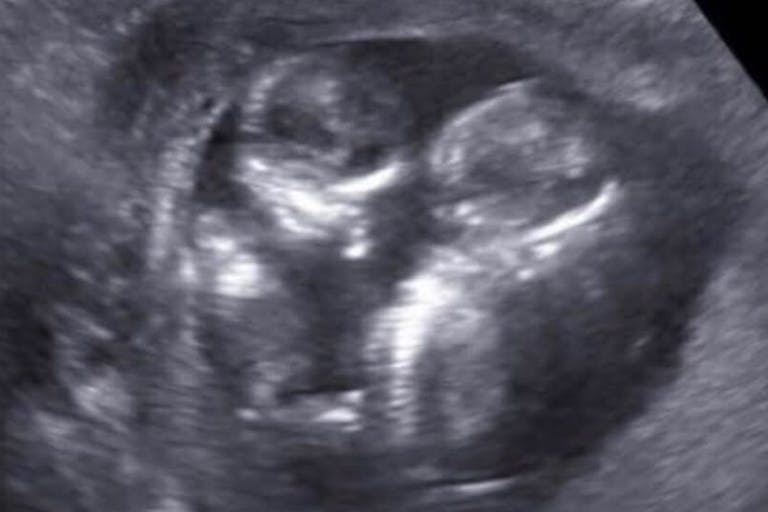

“They would print out the sonogram pictures and just to see his little face (was amazing). And he had a little personality — they kept trying to see him from the front and every time he would just turn around and show his butt,” she said. “It gave us hope.”